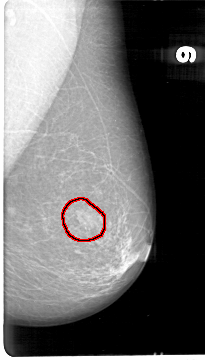

D_4042_1.LEFT_MLO

LEFT_CC LINES 5386 PIXELS_PER_LINE 3181 BITS_PER_PIXEL 12 RESOLUTION 43.5 OVERLAY

LEFT_MLO LINES 5386 PIXELS_PER_LINE 3061 BITS_PER_PIXEL 12 RESOLUTION 43.5 OVERLAY

FILE: D_4042_1.LEFT_MLO.OVERLAY

TOTAL_ABNORMALITIES 1

ABNORMALITY 1

LESION_TYPE MASS SHAPE OVAL MARGINS OBSCURED

ASSESSMENT 0

SUBTLETY 5

PATHOLOGY BENIGN

TOTAL_OUTLINES 1

BOUNDARY